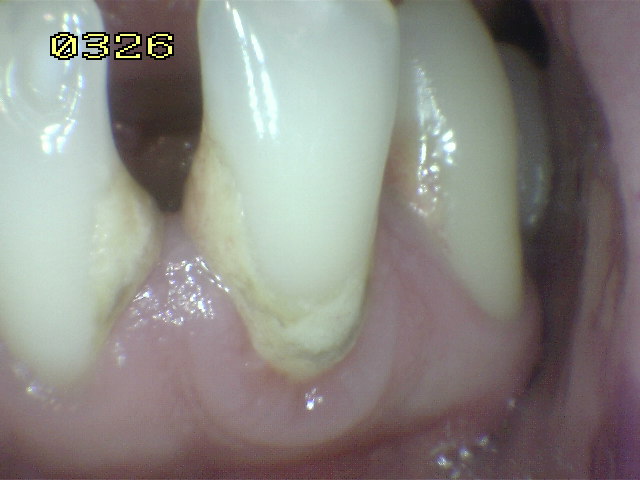

Debe eliminar la placa bacteriana de las

superficies (UCE) unión cemento-esmalte por

medio del cepillado mecánico o cepillo dental, para poder observar áreas de

desmineralización si las hubiere. Ver

círculos en amarillo.